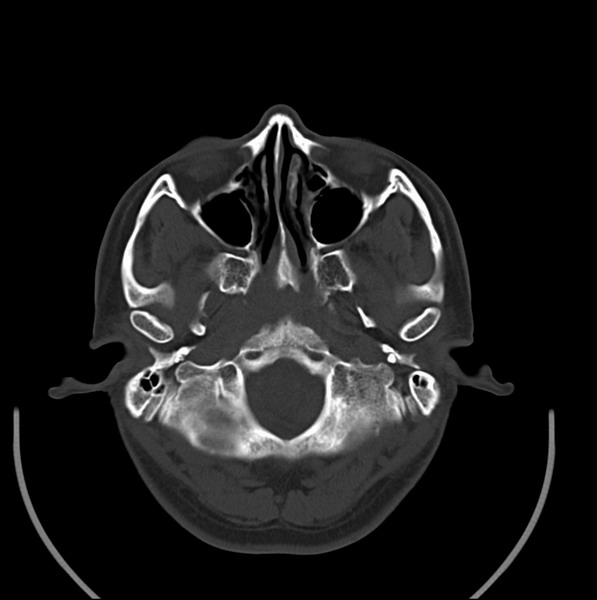

男、30、发现鼻咽部肿瘤侵犯海绵窦,未发现明显淋巴肿。请问国内那家医院治疗鼻咽部肿瘤最好?手术以何种方式为主?病灶可否全部切除?急切期待的大家的帮助。

扫描示鼻咽腔不对称,中度狭窄,右侧咽隐窝消失,局部软组织肿块,鼻咽右侧壁增厚形成肿块,突入鼻咽腔,肿块平扫呈等密度,肿块向深部侵润,右侧翼内外肌受侵,右侧咽旁间隙变窄;向后生长,头长肌界线欠清,向后上生长侵犯同侧颈动脉鞘区。双侧海绵窦增宽,内见软组织影与鼻咽部肿块相连。考虑鼻咽癌。鼻咽癌主要是放射治疗,且效果较好;到当地有治疗设备较大医院治疗即可。